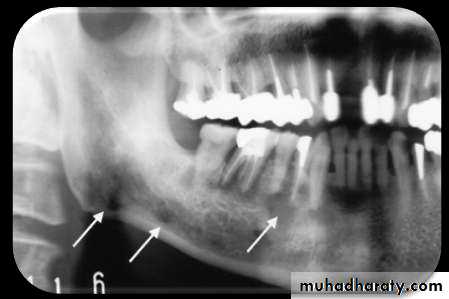

• PROLIFERATIVE PERIOSTITIS

RADIOLOGY

• Radiopaque laminations of bone roughly parallel each other & underlying• cortical surface.

• Laminations may vary from 1-12 in number.

• Radiolucent separations often are present between new bone & original

• cortex.• PROLIFERATIVE PERIOSTITIS